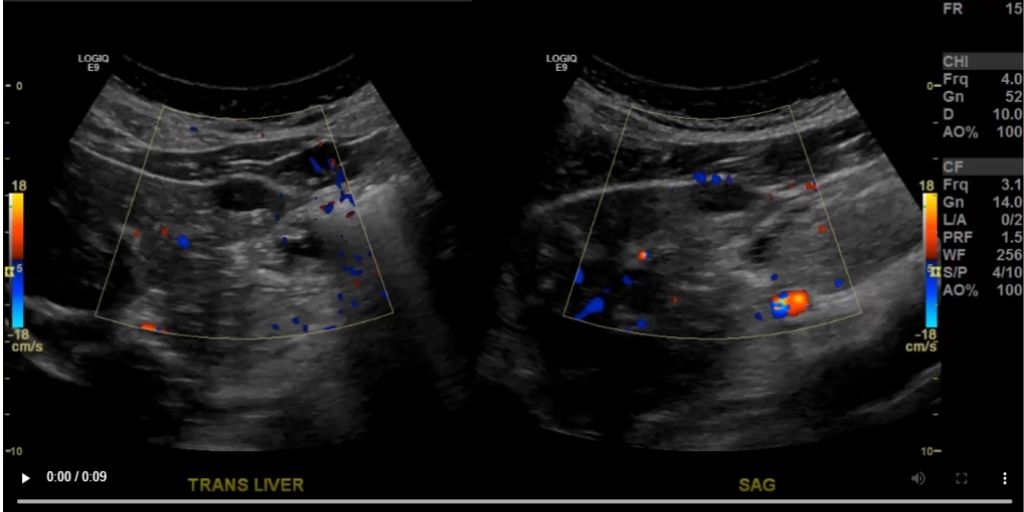

· Making it easy to capture and integrate vital medical images and data during endoscopy procedures and make them available from within Epic Lumens

· Eliminating information silos and allowing clinicians to access images from any specialty or department

· Enhance clinical productivity and patient outcomes by providing a single view of all patient information, including images and video